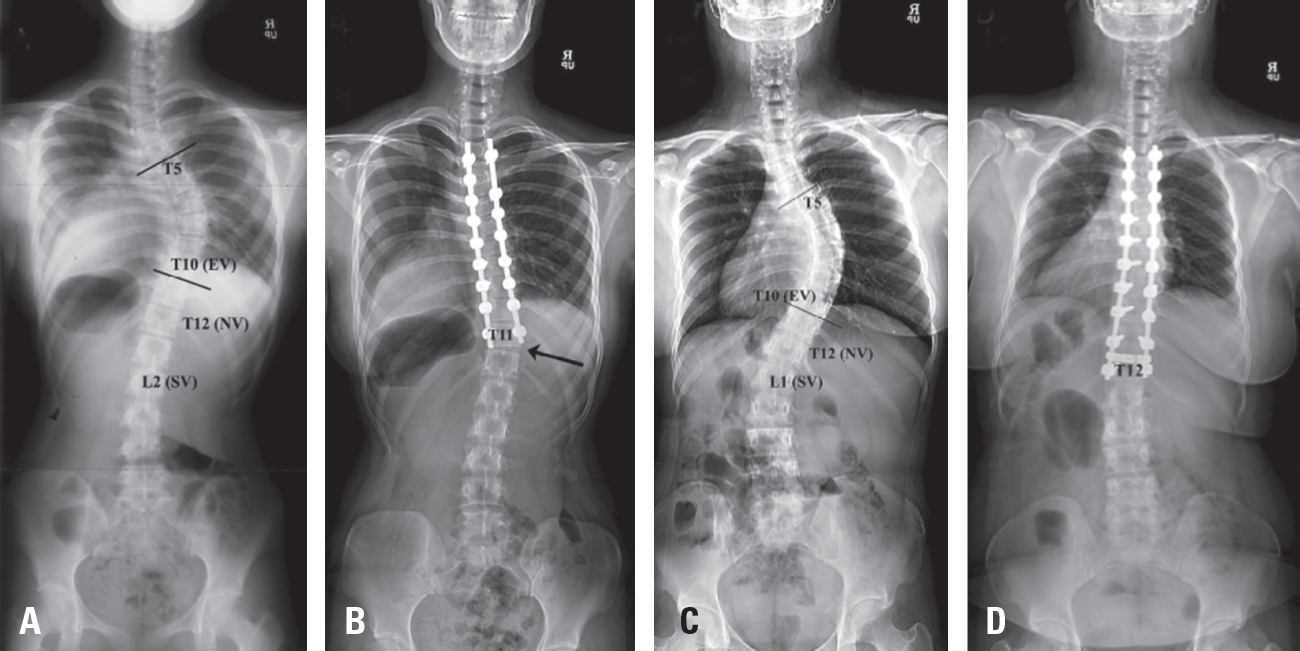

Fig. 5.Adding-on occurs when fusion does not extend to the neutral vertebra (NV). Both (A) and (C) presented with a King type 3 curve with the neutral vertebra at T12. Case (C), in which T12 was selected as the LIV, was treated appropriately like case (D) without any adding-on. In contrast, case (A) did not adhere to the appropriate treatment principles, and, as illustrated in case (B) subsequent lumbar vertebral deviation and disc angulation developed, consistent with the adding-on phenomenon.